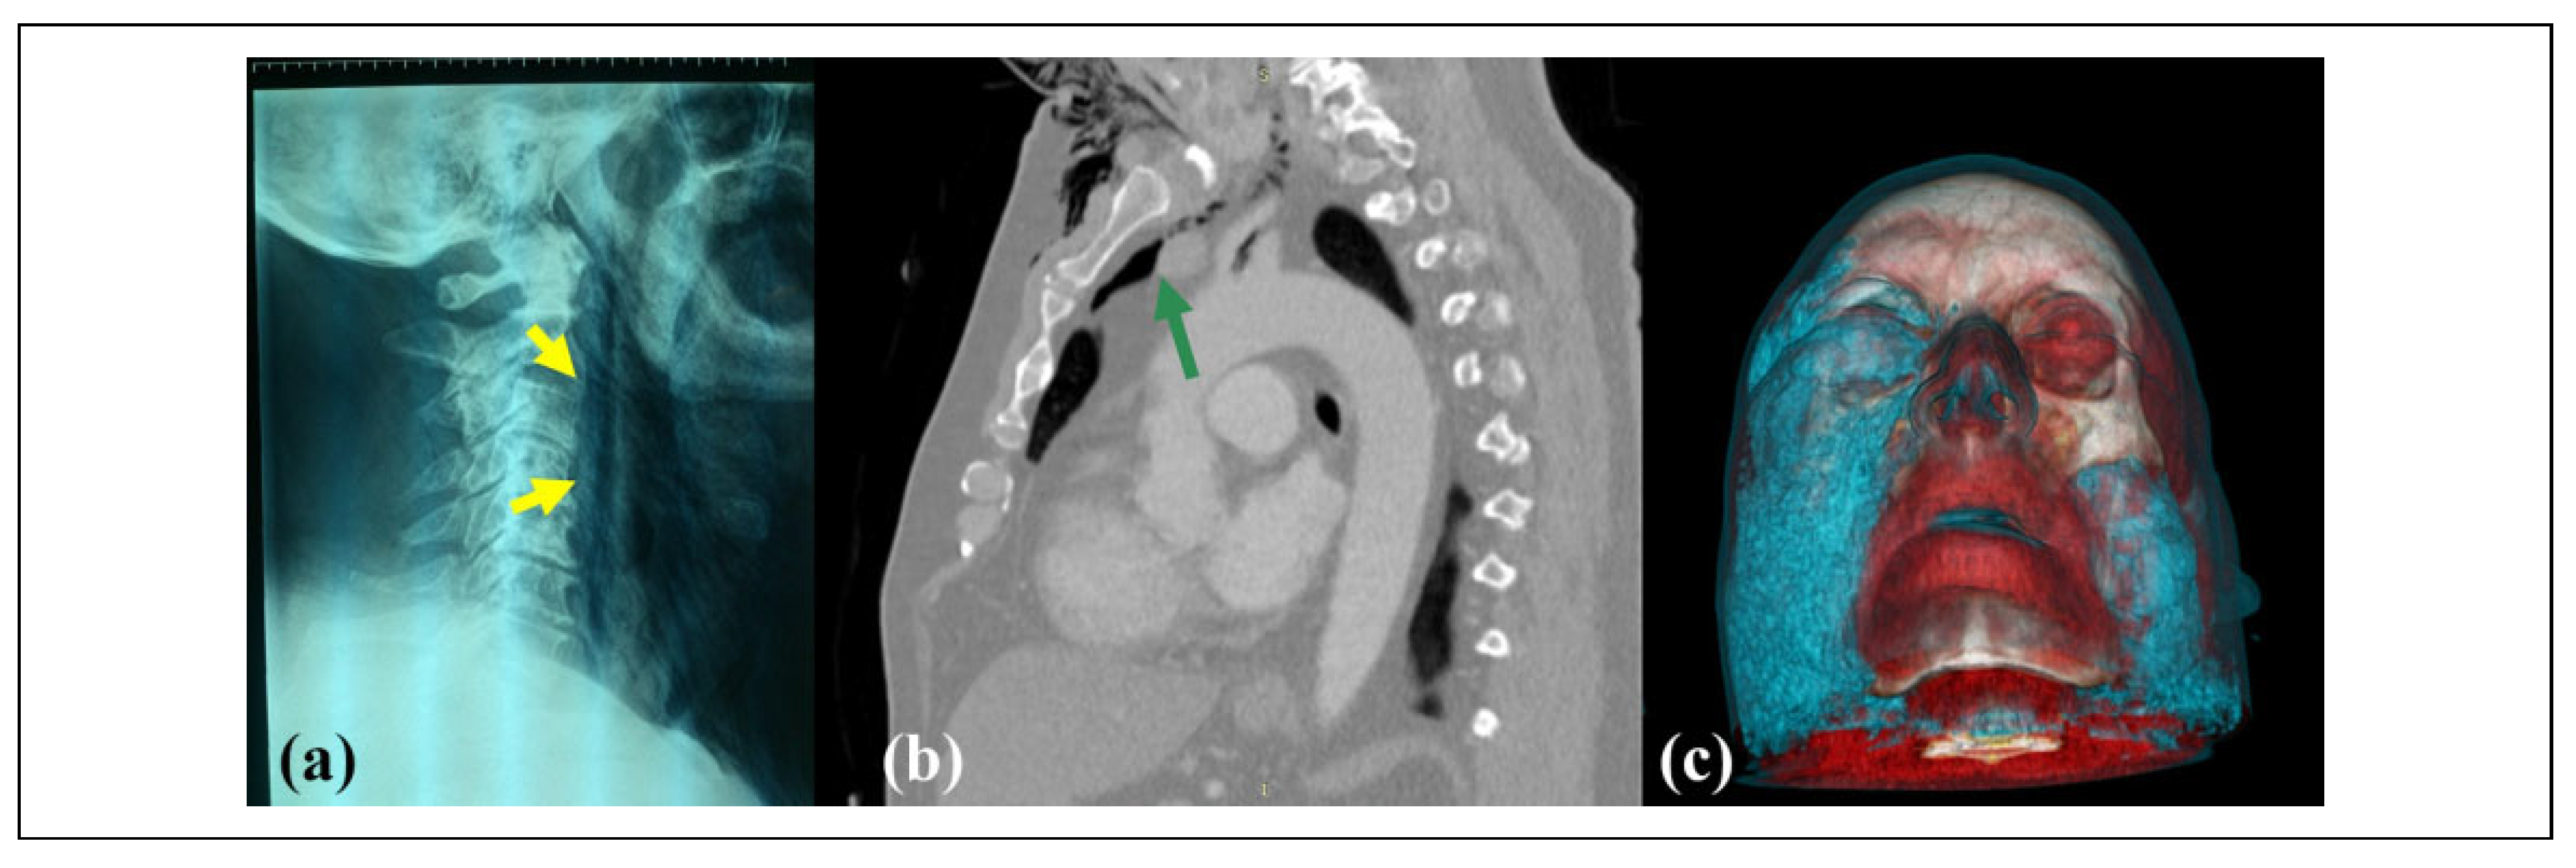

![]() |